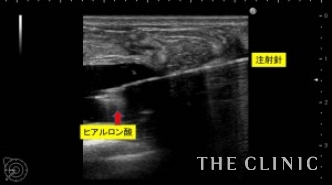

昨年12月にヒアルロン酸豊胸の手術を受けたが、2ヶ月前からしこりが気になり始めたため手術を受けたクリニックに相談に行くと、しこり除去後2~3ヶ月経たないと脂肪注入は出来ないと言われたそうです。患者様はそんなに待てないとのことでヒアルロン酸除去とCRF豊胸のご相談で当院にいらっしゃいました。エコーで確認すると、乳腺と大胸筋の間にヒアルロン酸がたくさん残っており、一部カプセルを形成してしこりになっていました。CRF豊胸を行う前にヒアルロン酸を溶解除去しないと、コンデンスリッチファットの定着が下がる可能性があるため、エコー下に確実に吸引除去する必要があります。ヒアルロン酸が少量であれば、ヒアルロン酸除去と同時にCRF豊胸が可能ですが、この方は大量にヒアルロン酸が残っていたため、まずはヒアルロン酸除去を行いました。

16ゲージの注射針を確実にヒアルロン酸のしこりに入れて、ヒアルロニダーゼ(ヒアルロン酸溶解剤)を注入し、溶けたヒアルロン酸は吸引除去します。

両側合わせて150㏄のヒアルロン酸を吸引除去しました。

ヒアルロン酸注入によるしこりのエコー診断カルテ